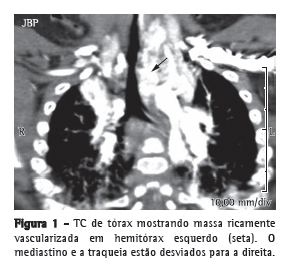

A TC de tórax, laringe e traqueia mostrou uma massa heterogênea, ricamente vascularizada no hemitórax esquerdo (Figura 1), sem malformação cardíaca associada. A broncoscopia rígida realizada sob anestesia geral revelou uma grande massa pulsátil que obstruía aproximadamente 80% da laringe e traqueia (Figura 2a; Vídeo 1 ). O diagnóstico de hemangioma fundamentou-se nos aspectos radiológicos e endoscópicos. Não foi realizada biópsia devido ao risco de sangramento.